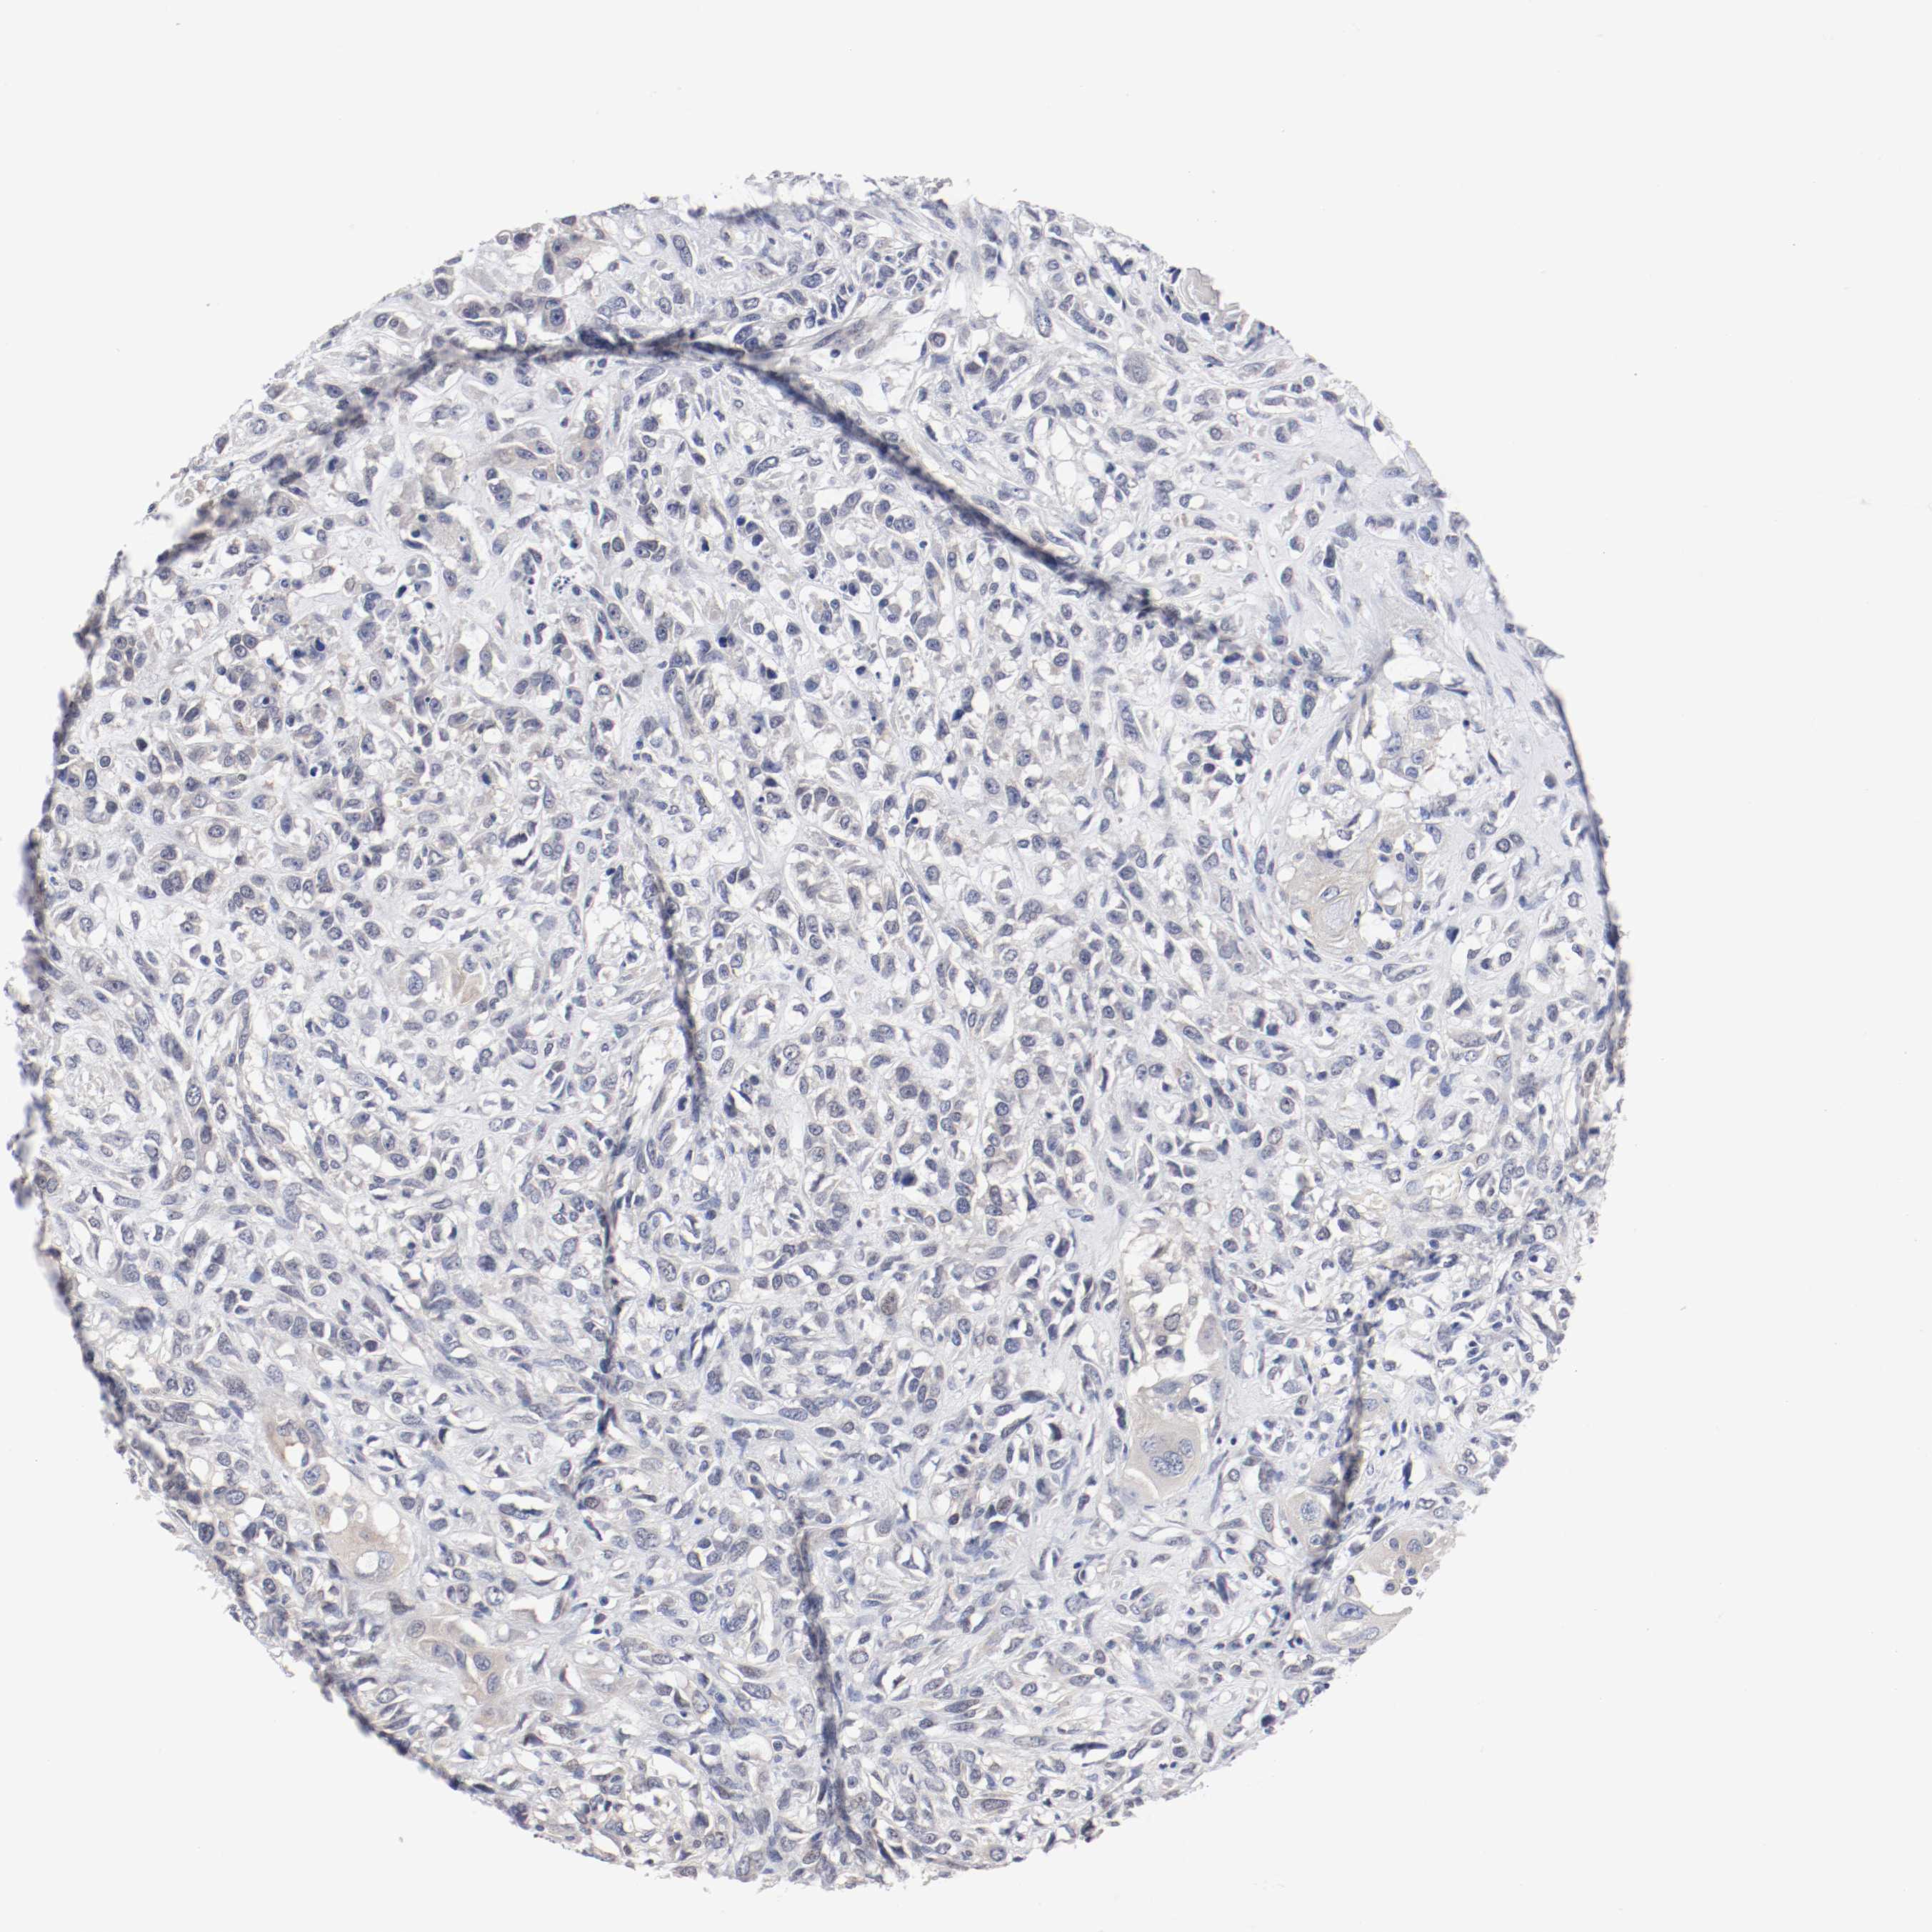

HEAD AND NECK CANCER - Protein expressioni

A mouse-over function shows sample information and annotation data. Click on an image to view it in a full screen mode. Samples can be filtered based on level of antibody staining by selecting one or several of the following categories: high, medium, low and not detected. The assay and annotation is described here.

Antibody stainingi

Antibody staining in the annotated cell types in the current human tissue is reported as not detected, low, medium, or high, based on conventional immunohistochemistry profiling in selected tissues. This score is based on the combination of the staining intensity and fraction of stained cells.

Each image is clickable and will lead to virtual microscopy that enables deeper exploration of all samples and also displays staining intensity scores, fraction scores and subcellular localization as well as patient and tissue information for each sample.

Antibody HPA003648

Staining

High

Medium

Low

Not detected

Intensity

Strong

Moderate

Weak

Negative

Quantity

>75%

75%-25%

<25%

None

Location

Nuclear

Cytoplasmic/membranous

Cytoplasmic/membranous,nuclear

Squamous cell carcinoma, NOS

Neoplasm, malignant, NOS

Carcinoma, NOS